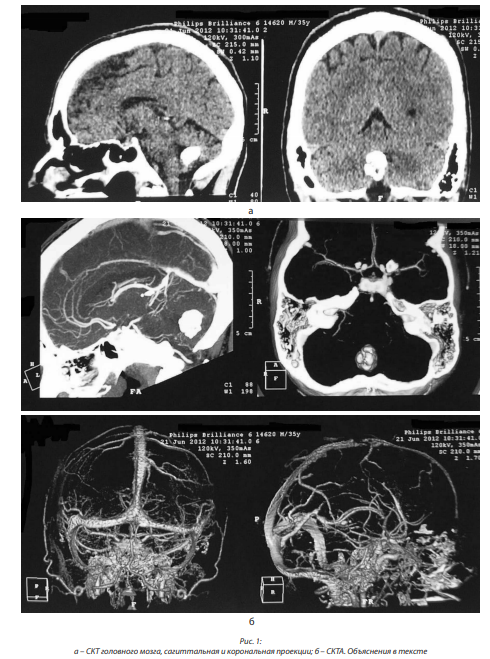

Удалил три зуба на верхней челюсти, принимал карбамазепин по три таблетки в день, однако эффекта не отмечал. Летом 2016 г. консультирован в 1-м нейрохирургическом отделении ГМПБ № 2. При МРТ головного мозга и ствола выявлен вазоневральный конфликт с правым тройничным нервом. В августе 2016 г. выполнена двухэтапная операция декомпрессии правого тройничного нерва с выраженным положительным эффектом (боль исчезла и не беспокоит). Начиная с марта-апреля 2017 г. заметил неустойчивость при ходьбе, которая постепенно прогрессирует, особенно с конца мая; отметил постепенное увеличение площади онемения участков левой половины тела, при этом нога онемела полностью (в течение месяца). При ходьбе стал пользоваться палочкой. Повторно поступил в нейрохирургическое отделение для обследования. При МРТ головного мозга от 21.06.2017 выявлены очаговые изменения в области олив продолговатого мозга, характерные для ГДО (рис. 6, а, б).

Таким образом, клиническая картина представлена миоклонусом мягкого нёба, бульбо-псевдобульбарным синдромом, легкой пирамидной недостаточностью в ногах, снижением вибрационного чувства в нижних конечностях; смешанной атаксией, преимущественно статико-локомоторной, а также динамической в левых конечностях, сенситивной и лобной атаксией. При МРТ головного мозга наряду с признаками дисциркуляторной энцефалопатии выявляются изменения в продолговатом мозге по типу гипертрофии олив.

В июне 2017 г. выполнена МРТ головного мозга, заключение: МР-картина гипертрофической оливарной дегенерации (в продолговатом мозге с обеих сторон выявляются симметричные участки измененного МР-сигнала, гиперинтенсивные на Т2 ВИ и FLAIR размерами 15×7 мм справа и 14×7 мм слева, с четкими контурами, без перифокального отека; продолговатый мозг на этом уровне слегка вздут; боковые и III желудочки расширены, симметричны; субарахноидальные пространства конвекса и базальные цистерны не расширены) (рис. 7, а, б).

У третьей пациентки нёбный миоклонус и атаксия развились поздно, через 8 лет после тяжелого ушиба среднего мозга, и также сопровождались наличием двусторонней ГДО.